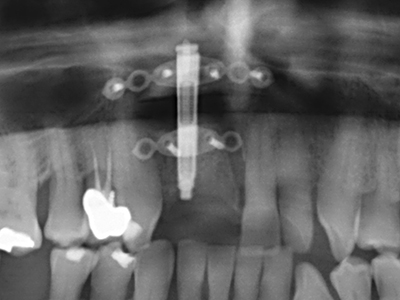

As shown in the past, basically any bone surgery procedure represents a possible indication for piezo surgery. Thus preparation of the mobile segment in distraction osteogenesis (Fig. 23-25) and sandwich osteotomy uses special attachments without endangering the blood supply to the crestal section, which is essential for the success of both techniques (Gonzalez-Garcia, Diniz-Freitas et al. 2008).

For removal of an implant, a vestibular bone cover that is replaced after removal of the implant screw can be prepared to retain the contour of the alveolar ridge.

There are additional applications in sinus surgery. Pathologies and foreign bodies can be removed from the sinus after concentric preparation of a generally trapezoid bone cover in the facial sinus wall. The bone cover is repositioned on conclusion of the intra-antral operation component and secured by wedging or adaptive sutures to prevent dislocation.

Purely orthodontic indications include orthognathic surgery, genioplasty (Fig. 27-30) and orbital decompression in patients with advanced endocrine orbitopathy as a result of Basedow’s disease (Ponto, Zwiener et al. 2014). Piezo devices are also used in maxillofacial surgery and to remove tumours at the base of the skull in various hospitals.